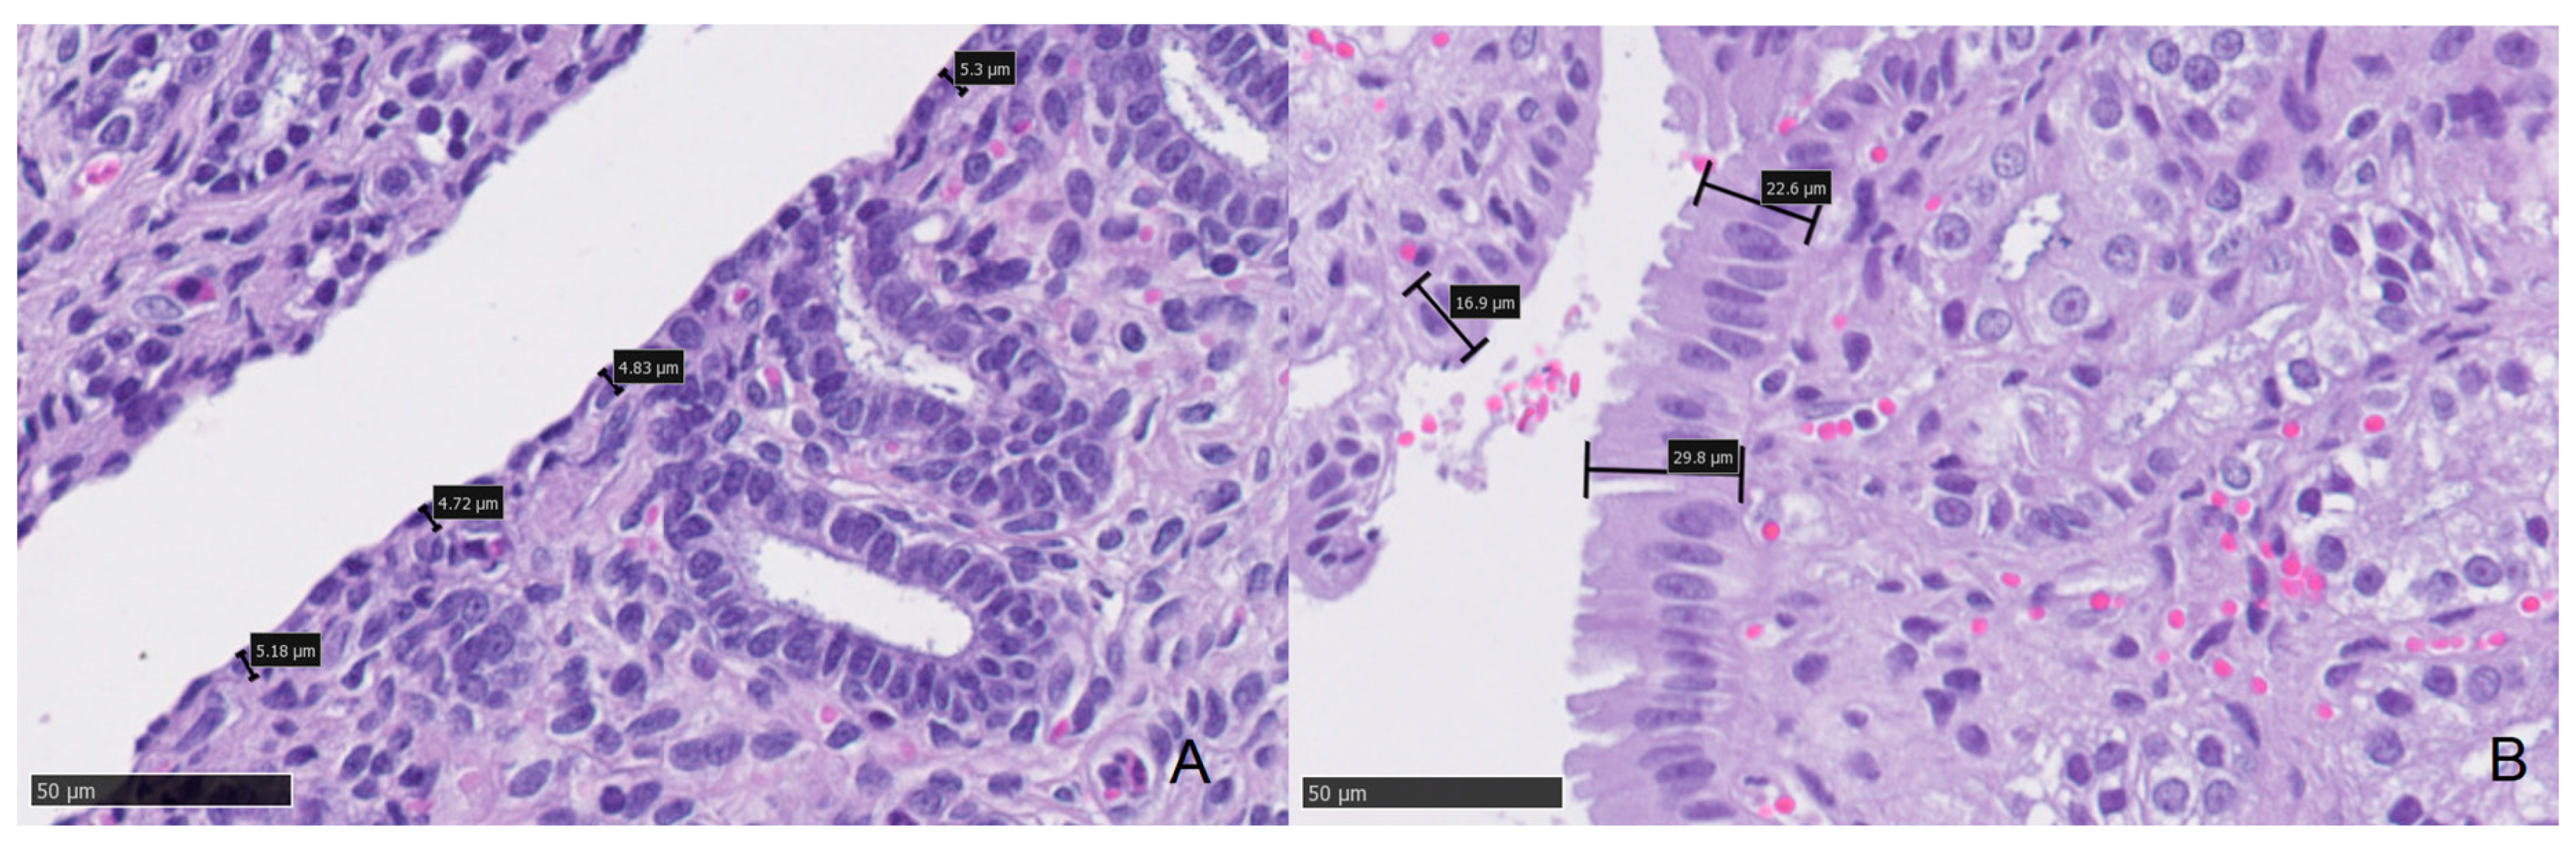

3.3. Histology

| Low Progesterone | High Progesterone | ||||||

|---|---|---|---|---|---|---|---|

| Median | Minimum | Maximum | Median | Minimum | Maximum | p | |

| Epithelial Height (cm) | 7.95 | 5.22 | 11.40 | 15.23 | 6.36 | 31.22 | 0.000 |

| Diameter 1 (cm) | 53.99 | 28.03 | 89.47 | 86.97 | 40.00 | 158.33 | 0.039 |

| Diameter 2 (cm) | 37.67 | 22.33 | 54.57 | 53.04 | 23.39 | 90.36 | 0.039 |

| Mean Diameter (cm) | 45.82 | 25.18 | 68.74 | 70.00 | 36.10 | 124.35 | 0.012 |

| Glandular Density (glands/400×) | 6.12 | 0.95 | 11.40 | 7.49 | 0.50 | 18.20 | 0.278 |

| Neutrophil (in 10 fields 400×) | 0.49 | 0.00 | 4.60 | 0.16 | 0.00 | 0.60 | 0.053 |